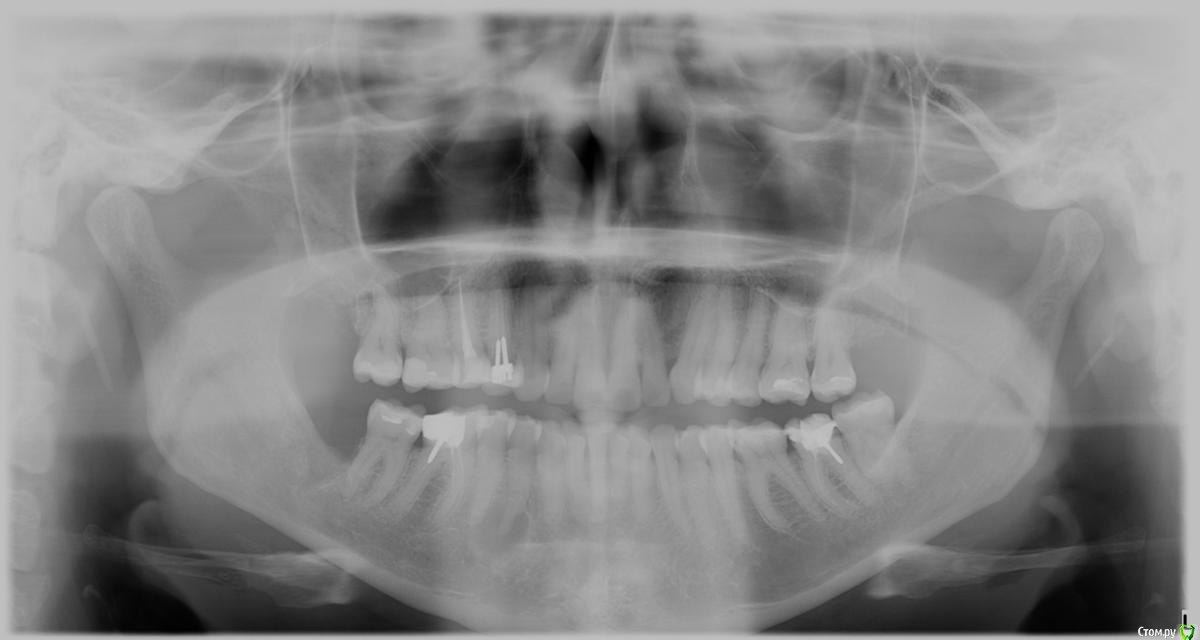

good customer Опубликовано 6 июля, 2016 Поделиться Опубликовано 6 июля, 2016 Здравствуйте, уважаемые Врачи! В мае 2016г на панорамном снимке была обнаружена киста четверки (не болит, не лечили, не били).В июне была сделана кт (в др клинике), где подтвердили кисту зуба. Врач порекомендовал наблюдать в течение 6 мес.Я усомнилась.Сегодня вновь посетила первую клинику и сделали кт. Киста подтвердилась, но не зуба.Как я поняла, киста в тканях проросла так далеко, что истончилась кость и скоро будет задет нерв.Очень благодарна терапевту, что не стал вскрывать зуб, а хирург выписал направление на консультацию в МГМСУ на Вучетича. Успела в институт дозвониться в конце рабочего дня- сказали, что запись на август и положили трубку.Скорее всего, на форуме есть чл-хирурги.Уважаемые Врачи, посмотрите, пожалуйста, мои снимки.Панорамный снимок и отсканированную распечатку фрагмента зуба кт (есть полная версия на диске).Подскажите, пожалуйста, кому из врачей в данном институте можно довериться (или в др лечебном заведении)?Спасибо. Ссылка на комментарий

kladoffka Опубликовано 8 июля, 2016 Поделиться Опубликовано 8 июля, 2016 Обычная гранулема, имхо. Чего там делать члх? Оо 3 Ссылка на комментарий

good customer Опубликовано 8 июля, 2016 Автор Поделиться Опубликовано 8 июля, 2016 В частной стоматологической клинике от меня отказались. выдвинуты предположения, что это киста к зубу не имеет отношения. даже рассказали про онкологию. В практике врачей такого не было , поэтому направили в члх. Ссылка на комментарий

good customer Опубликовано 10 июля, 2016 Автор Поделиться Опубликовано 10 июля, 2016 Добрый вечер, уважаемые Врачи! Нашла панорамный снимок от 2014г. кисты, вроде, не было.... Ссылка на комментарий

Alejandro Опубликовано 12 июля, 2016 Поделиться Опубликовано 12 июля, 2016 Приглядитесь: на этом снимке образование тоже есть. Проверили зуб на витальность? 1 Ссылка на комментарий